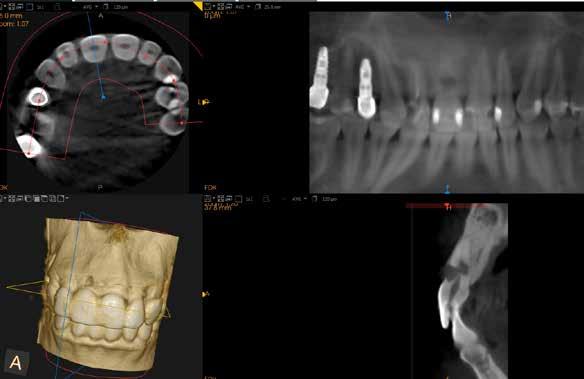

1. ábra: Megfelelő szájhigiénia – panorámaröntgen. 2. ábra: A 2.5, 2.6 és 2.7-nek megfelelő terület a röntgenfelvételen.

és jelentős mobilitással rendelkezett. A radiológiai vizsgálat után egyértelműen látszódott, hogy a fogon még nem végeztek gyökérkezelést. A 2.6-os és 2.7-es fogaknak megfelelő területen az arcüreg kiterjedése jelentős volt, vertikális csontmennyiség szignifikánsan csökkent (1. és 2. ábra).